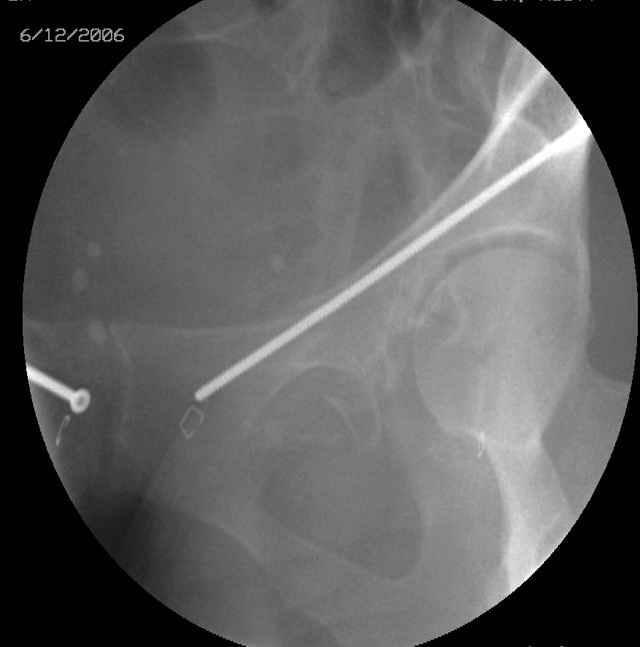

We seek the starting site (after reduction) with a thin wire guided by fluoroscopic imaging as the obturator-outlet combination image and also the inlet image...engage the wire tip into bone, incise around the wire, apply a soft tissue protection sleeve of known length over the wire, remove the wire, exchange thru the sleeve with an appropriate diameter drill (I use a 3.5mm most often), drill the glide pathway above and behind the joint to the fracture, exchange for a calibrated appropriate diameter drill, oscillate within the ramus to the pubis, measure depth using the calibrated drill and known sleeve length, do the math, remove the drill and insert screw, tighten, squirt the hole, close, stress the fixation, supplement if needed.